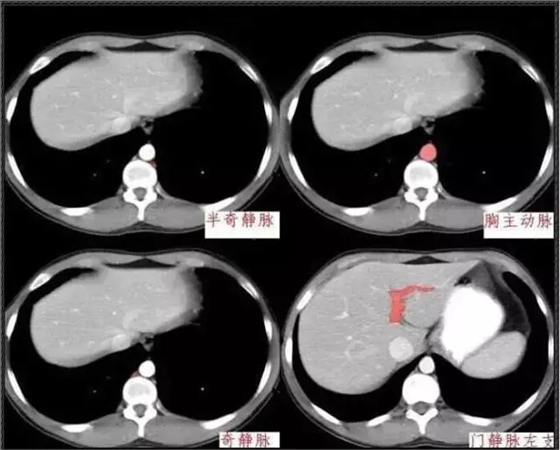

640.webp.jpg

640.webp (1).jpg

640.webp (2).jpg

640.webp (3).jpg